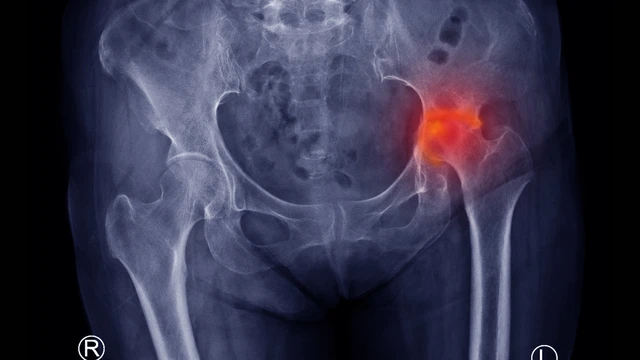

Nguyên nhân gây đau mỏi khớp háng có thể do chấn thương cơ học hoặc do các bệnh lý liên quan đến xương khớp. Khi xác định rõ nguyên nhân sẽ giúp đưa ra phác đồ điều trị hiệu quả nhất, tránh gây ảnh hưởng đến chất lượng cuộc sống của người bệnh.